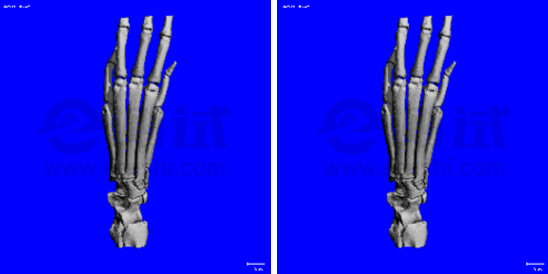

3. 骨質(zhì)疏松模型小鼠三維重建

a3370ee4dda9417dc558b2d3003e9cb4

5. 正常小鼠踝關(guān)節(jié)/關(guān)節(jié)炎小鼠踝關(guān)節(jié)

41a6dae63109cdeb88f6e47b8475c3e4